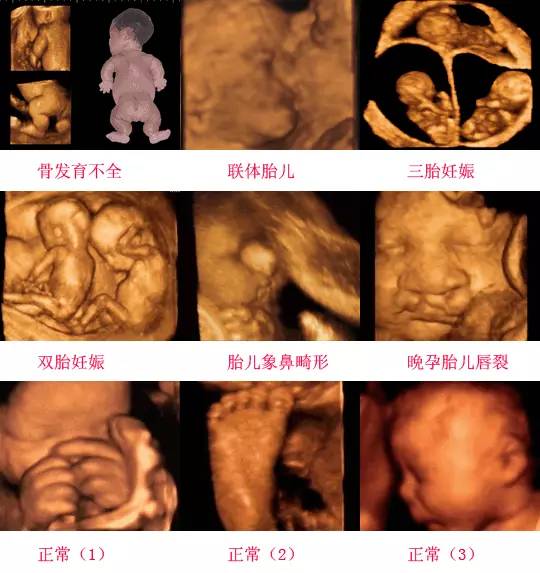

摘要:通過四維彩超技術,我們能夠清晰地觀察到胎兒蛋蛋的發(fā)育情況,開啟早期胎兒生殖器官發(fā)育的探索之旅。這項技術能夠展示胎兒生殖器官的立體圖像,幫助醫(yī)生了解胎兒生殖系統(tǒng)的發(fā)育狀況,為早期發(fā)現(xiàn)潛在問題提供了可能。這不僅有助于保障胎兒的健康,也為優(yōu)生優(yōu)育提供了科學依據(jù)。

四維彩超是一種先進的醫(yī)學影像技術,通過實時觀察胎兒在母體內的活動情況,為醫(yī)生提供了豐富的診斷信息,在四維彩超下,我們可以清晰地觀察到胎兒的蛋蛋(睪丸)的形態(tài)、位置和大小等特征,胎兒蛋蛋是男性生殖系統(tǒng)的重要組成部分,對于胎兒的生長發(fā)育具有重要意義。

在四維彩超下,胎兒蛋蛋呈現(xiàn)出特定的形態(tài)和外觀,通常情況下,胎兒蛋蛋呈現(xiàn)出圓形或橢圓形,表面光滑,內部回聲均勻,隨著胎兒的發(fā)育,蛋蛋會逐漸增大,并呈現(xiàn)出明顯的性別特征,醫(yī)生可以通過四維彩超技術,對胎兒蛋蛋的大小、形態(tài)和位置進行評估,以判斷胎兒生殖系統(tǒng)的健康狀況。

胎兒蛋蛋的發(fā)育是一個復雜的過程,受到多種因素的影響,在胎兒發(fā)育的早期階段,蛋蛋位于腹腔內,隨著胎兒的生長發(fā)育,蛋蛋逐漸下降至陰囊,這個過程受到激素、遺傳和環(huán)境等多種因素的影響,在四維彩超的觀測下,我們可以實時了解胎兒蛋蛋的發(fā)育過程,及時發(fā)現(xiàn)異常情況并采取相應的治療措施。

四維彩超技術在評估胎兒蛋蛋發(fā)育方面具有重要意義,通過四維彩超,醫(yī)生可以實時觀察胎兒蛋蛋的形態(tài)、位置和大小等特征,了解胎兒生殖系統(tǒng)的發(fā)育情況,四維彩超還可以幫助醫(yī)生發(fā)現(xiàn)可能的異常情況,如睪丸未降、睪丸囊腫等,為及時采取治療措施提供依據(jù)。